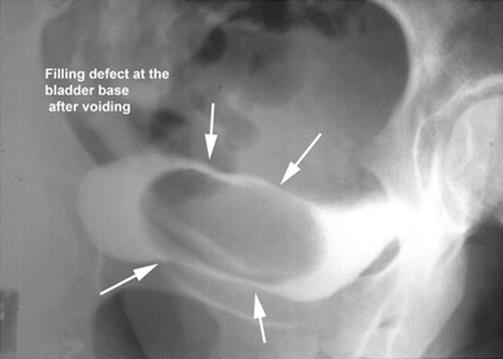

8.3 Ectopic Ureterocele Presenting as a Vaginal Cyst

The patient, 23 years old, presented with difficulty in emptying the bladder, recurrent urinary infection, and distal urethral pain. Figures 8.11, 8.12, 8.13, and 8.14 illustrate the finding of an ectopic ureterocele. The patient had a side-to-side anastomosis of the ureters, with ligature of the affected ureter. The urethral cyst and her voiding dysfunction were corrected and she remained asymptomatic.

Fig. 8.14

A post-void film shows a large cystic filling defect of the bladder base, typical of an ectopic ureterocele. The arrows outline the cyst